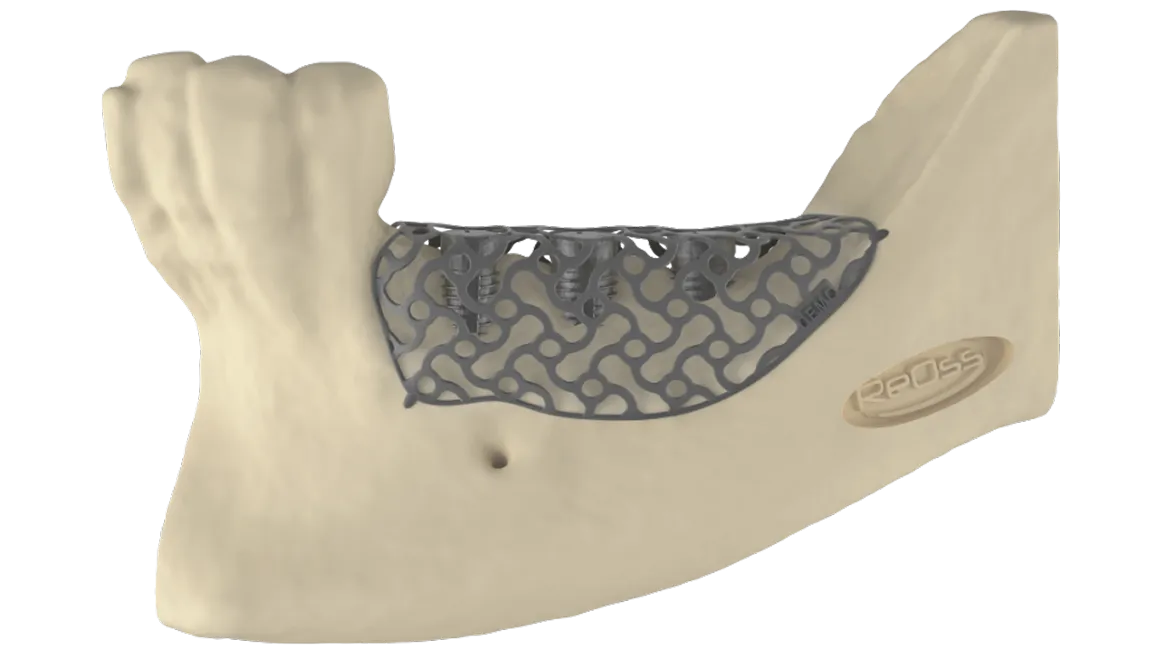

TRÓJWYMIAROWA REKONSTRUKCJA WYROSTKA ZĘBODOŁOWEGO PRZY UŻYCIU INDYWIDUALNIE DRUKOWANYCH SIATEK TYTANOWYCH YXOSS ReOss

To kolejna metoda umożliwiająca precyzyjną odbudowę zadanego kształtu tkanki kostnej przy użyciu standardowych materiałów kościotwórczych, kości własnej lub PRF oraz zewnętrznego rusztowania w postaci siatki z biozgodnego stopu tytanu. Siatka jest indywidualnie projektowana w technologii CAD CAM i następnie drukowana dla konkretnego przypadku.

Dotychczas stosowane stabilizatory zewnętrzne w formie siatek tytanowych używane do regeneracji kostnej lub w zabiegach odtwórczych w chirurgii szczękowo-twarzowej uwzględniały materiały ręcznie doginane i formowane podczas zabiegu operacyjnego. Zastosowanie technologii CAD CAM dla potrzeb druku materiałów przeznaczonych do indywidualnej rekonstrukcji kostnej znacznie poprawiło precyzję i jakość uzyskiwanych efektów. Wdrożenie biozgodnych stopów tytanu do druku siatek zdecydowanie ograniczyło odsetek powikłań zapalnych.

Precyzja projektu druku siatki bazuje na dokładności odwzorowania kształtu kości w stożkowej tomografii komputerowej CBCT, co zapewnia ich dobre przyleganie do podłoża kostnego oraz ogranicza powstawanie powikłań w postaci obnażania się siatek. Precyzja projektu oraz materiał, z którego wykonana jest siatka (biozgodny stop tytanu), powodują, że obnażenie się siatki nie zaburza procesu gojenia i regeneracji kostnej.

Wymaga jedynie większej ilości kontroli pozabiegowych oraz wzmaga czujność higieniczną zarówno ze strony lekarza, jak i pacjenta. Ten rodzaj odbudowy kostnej stosowany jest w sytuacjach złożonych, trójwymiarowych 3D ubytków kości, przy których standardowe metody odbudowy są niewystarczające. Ilość kości, którą możemy uzyskać, stosując tę metodę, to nawet kilka centymetrów sześciennych.

Metoda rekonstrukcji kostnej w oparciu o indywidualnie drukowane siatki z tytanu dla implantacji wszczepów śródkostnych stosowana jest najczęściej jako dwuetapowa. W pierwszym etapie odbudowywana jest kość, natomiast implanty wszczepiane są po okresie 4–6 miesięcy. Na wgojenie implantów oczekujemy od 4 do 6 miesięcy w zależności od miejsca ich lokalizacji. Siatka tytanowa po spełnieniu swojej funkcji rusztowania dla odbudowującej się kości jest następnie usuwana w dniu wszczepienia implantu. Jeżeli kość spełnia odpowiednie warunki, istnieje możliwość zastosowania modyfikacji siatki tytanowej, która umożliwia jednoczesne wprowadzenie implantów wraz z odbudową kostną.

Wariant ten skraca czas od pierwszego zabiegu do wykonania gotowych koron protetycznych na wprowadzonych implantach. Opisane schematy procedur regeneracyjnych wykazują znaczną innowacyjność, jeśli chodzi o wykorzystanie technologii cyfrowej w medycynie odtwórczej. Natomiast w codziennej praktyce chirurgicznej poprawiają precyzję, tempo oraz przewidywalność w świadczeniu usług polegających na odbudowie zniszczonych lub zdeformowanych ludzkich tkanek.